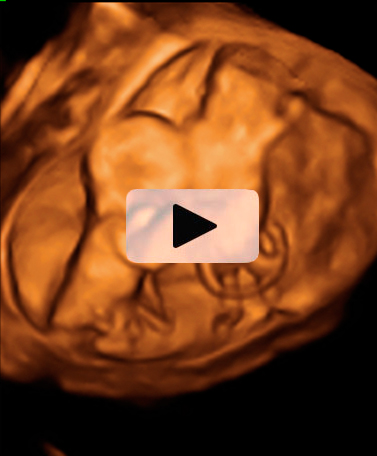

Los movimientos de estos gemelos de 12 semanas de gestación son extraordinariamente claros en la ecografía 4D. Los bebés mueven todo su cuerpo, especialmente brazos y piernas, adoptando multitud de posturas. Destaca el aspecto fieramente humano de los fetos, a pesar de su diminuto tamaño. Cuentan con dos placentas y dos bolsas independientes; la gruesa membrana de separación entre los bebés es visible en el registro ecográfico.

Ecografía 4D de gemelos de 12 semanas moviendo sus extremidades